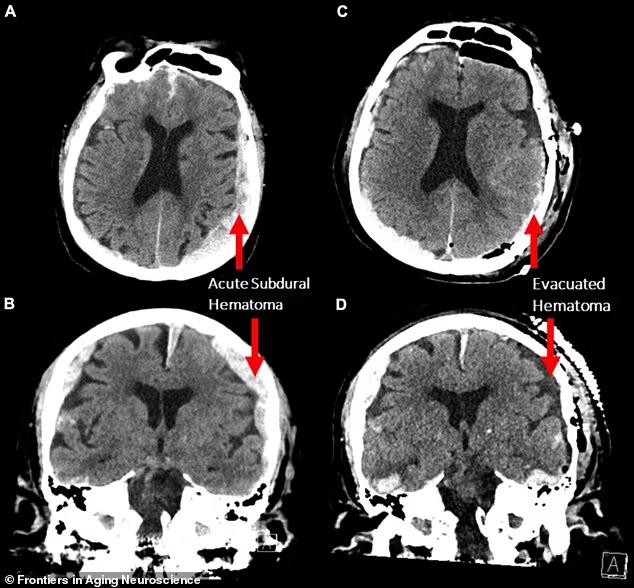

据最新一期《老龄化神经科学前沿》刊发的论文,加拿大神经科学家记录了一名87岁老人死亡时的大脑活动,揭示了一个快速的“记忆检索”过程。据悉,这是有史以来第一次记录濒临死亡的人脑活动。

加拿大不列颠哥伦比亚省温哥华综合医院收治了一名癫痫发作的87岁男子,患者心脏骤停。当神经科学家使用脑电图(EEG)为其检测和治疗时,无意中记录到一个濒临死亡的大脑活动。